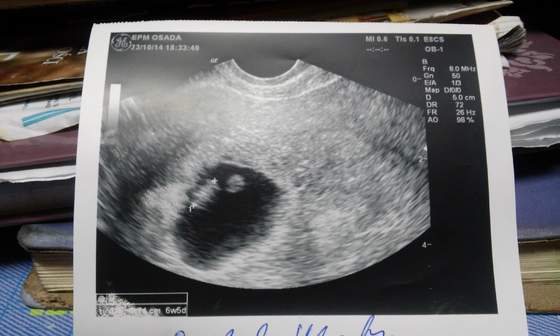

No i wizycie. Było już widać jak to pani doktor stwierdziła dzieciaczka. Pięknie bijące serduszko. Już zapomniałam jakie to cudowne uczucie. Kazała brać witaminy. Zleciła badania. No i naturalnie będziemy leczyć stan zapalny jest. Cieszę się ogromnie...;)

Wiec i ja w koncu dodam nasze zdjecie :) 20141024_143215[1].jpg

z serduszko bije i termin pokrywa sie z owu wiec bd miała urodzinowy prezent :)